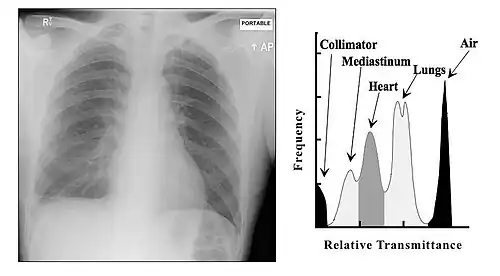

The overall effect of tissue attenuation is illustrated in the Figure 3.9 for the case of a chest radiograph. The exposed area of the patient consists in simplistic terms of air, tissues and bone and is surrounded by the rectangular collimator leaves. The air provides relatively negligible attenuation, while the bone provides substantial attenuation - and tissues provide an intermediate amount. As a result, bone can generate relatively high attenuation at lower X-ray energies and their X-rays shadows can interfere with the visualisation of the lung fields. Increasing the X-ray energy, by increasing the kV, will increase bone penetrability and reduce their shadowing effect. The overall result is a change in the prominence of features associated with different regions in the image histogram.

A typical image is shown in Figure 3.10. It can be seen that bone has a brighter shade of grey than that of the enveloping tissue and is brighter still than the surrounding air. This is the conventional method of displaying a radiograph such that higher photon attenuation is encoded as a brighter shade of grey.

From our earlier discussion, we can expect bone to absorb X-rays preferentially relative to the surrounding tissue and that the energy of these X-rays should have a strong influence on this absorption difference. It is this difference which generates contrast in radiographic images, and we can therefore expect contrast to reduce with increasing X-ray energy. We can also expect that the influence of scatter should be apparent at all X-rays energies.